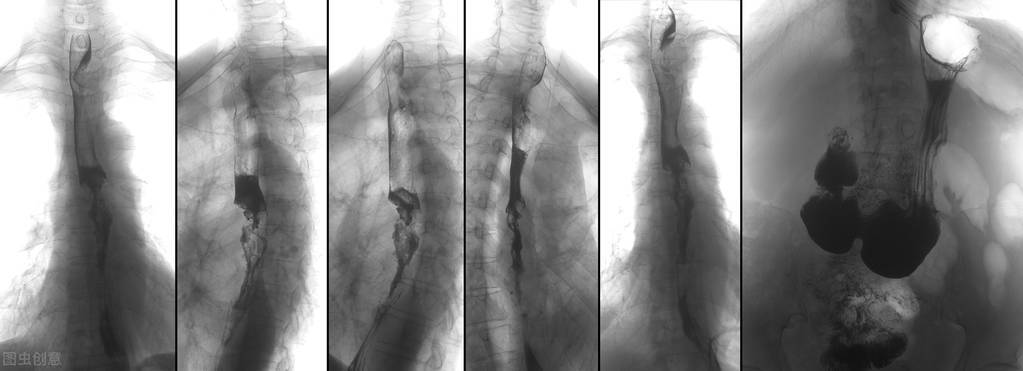

12、吞咽困难: 感觉喉咙有肿块是胃灼热的常见症状,但如果发现吃饭时难以吞咽,它可能表示 食管出了较为严重的问题。因为食道的实体瘤不断变大而阻塞了食管,所以患者会出现 吞咽困难、咽喉有异物感 等症状,那些长期重口味饮食、抽烟喝酒“凶”的人群要特别警惕食道癌,胃镜检查可以清晰地看到病变影像,早检查比什么都好。